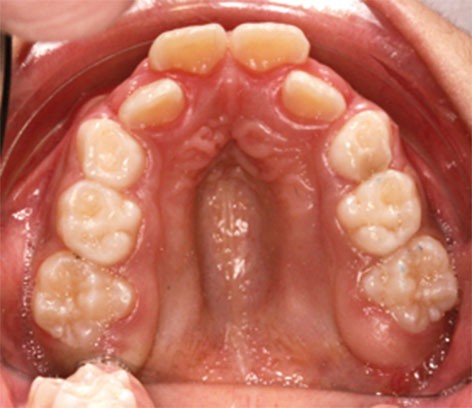

Au niveau dentaire, on évaluera la forme des arcades, la profondeur et l’étroitesse du palais, les malpositions et l’occlusion dans les trois sens de l’espace (fig. 2).

Certains phénotypes faciaux prédisposeraient au risque de troubles obstructifs du sommeil ; on décrit ainsi chez près de 34 % des enfants apnéiques une rétroposition mandibulaire, une hyperdivergence mandibulaire et un palais osseux ogival et profond.

Les dysmorphoses de ces jeunes patients s’accompagnent fréquemment de malocclusions dentaires, car, d’une part, l’insuffisance de développement des maxillaires occasionne un manque de place pour les organes dentaires, et, d’autre part, l’enfant adopte une posture linguale et mandibulaire de compensation, à l’origine d’anomalies secondaires.